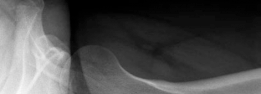

Radiographic assessment must be exhaustive. A standardized anteroposterior (AP) radiograph of the pelvis, centered over the symphysis pubis with neutral pelvic tilt and rotation, is mandatory. On this view, the LCEA, Tönnis roof inclination angle, and extrusion index are calculated. For instance, an LCEA of 18° and a roof inclination of 20° confirm severe lateral and superior uncoverage. A false profile view of the Lequesne and de Sèze is critical for assessing anterior coverage (anterior center-edge angle) and anterior joint space. Dunn 45° and 90° views, or a cross-table lateral, are utilized to evaluate the femoral head-neck junction for CAM morphology.

Advanced imaging is non-negotiable in the revision setting. A high-resolution MRI or MR arthrogram of the hip is required to assess the articular cartilage, the integrity of the ligamentum teres, and the state of the remaining labrum or capsular scar tissue. Anterolateral loss of joint cartilage is a frequent finding in dysplastic hips post-labral resection. Furthermore, a CT scan or MRI utilizing torsional sequences from the hip through the knee is essential to quantify femoral version. A measured femoral anteversion of 36° dictates that a derotational femoral osteotomy (DFO) must be incorporated into the surgical plan to restore normal biomechanics and prevent recurrent anterior subluxation post-operatively.

From an osseous perspective, the normal adult hip relies on a delicate balance of version and coverage. The acetabulum is typically anteverted approximately 15° to 20°, with a normal LCEA between 25° and 39°, and a roof inclination angle approaching zero. The proximal femur normally exhibits 10° to 15° of anteversion. In our complex instability cohort, this relationship is severely distorted. A patient may present with an LCEA of 18° (frank dysplasia) and a roof inclination of 20° (a steep, up-sloping sourcil), leading to a severely diminished weight-bearing surface area. When this is compounded by high femoral anteversion—such as 36° measured on MRI—the femoral head is driven anteriorly. This creates a functional anterior uncoverage that is exponentially worse than the radiographic coronal measurements imply.